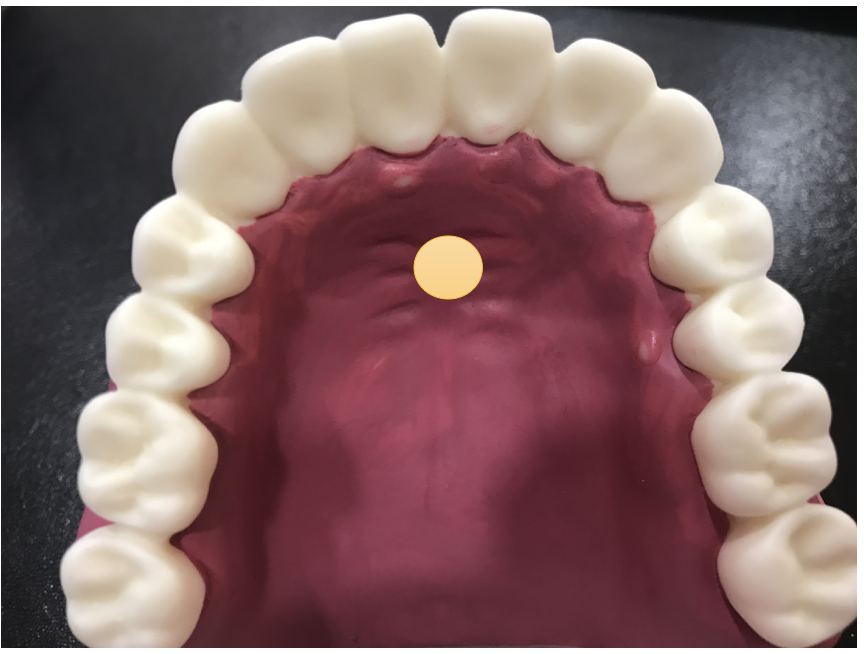

턱의 크기에 비해 혀가 지나치게 비대해져 있는 경우 혀 자체가 큰 경우보다 혀의 근력과 탄성이 떨어지면서 퍼져 있는 경우가 더 많습니다. 이러한 경우 운동을 통해 충분히 근력을 개선할 수 있습니다. 혀의 근력이 떨어져 있을 때 이를 기르기 위해서 도움이 되는 운동법을 두가지 알려드려 볼게요. 영상을 보시면서 반복해 보세요.